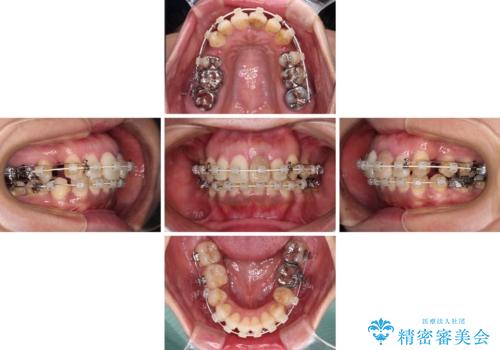

内側に倒れた前歯と口元の突出感 ワイヤー装置での抜歯矯正

- 歯列全体が内側に倒れ込んでいることと、口元の突出感を気にして来院された患者様です。

上下ともに歯列が狭窄しており、前方に突出している状態でした。

歯が重なるような叢生も認められたため、上下左右の第一小臼歯4本を抜歯して、口元が引っ込むように治療を行うこととしました。

口元を引っ込めることができたため、口を閉じるときに力が入っていて皺のよっていた顎先も、スムーズに閉じられるようになったことで力がかからなくなりました。

変色して気になっていた前歯も、オールセラミッククラウンで自然な色合いにすることができました。